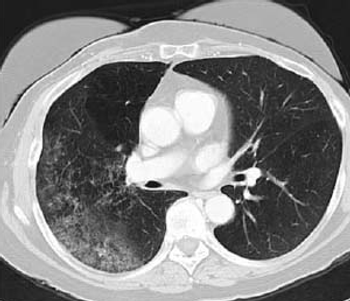

The NLST is a landmark trial demonstrating that implementation of low-dose CT screening lowers lung cancer–related mortality. We must put the study results and cost-effectiveness analyses in the context of the staggering statistics: up to 65% of lung cancer patients present with advanced-stage disease where treatments are often costly, toxic, and only palliative in nature.